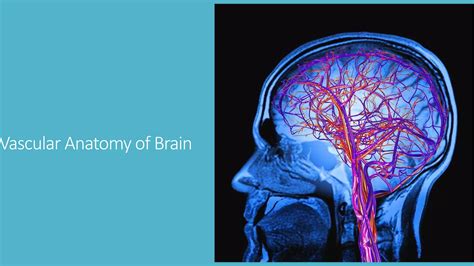

When you experience persistent, unexplained headaches, vision disturbances, or other neurological symptoms, your doctor may suggest advanced imaging to get to the bottom of the issue. One highly specialized tool used to visualize the complex network of blood vessels returning oxygen-depleted blood from the brain is Magnetic Resonance Venography (MRV). Understanding what the Magnetic Resonance Venography brain procedure entails can help alleviate anxiety and prepare you for what to expect during this diagnostic journey.

Magnetic Resonance Venography (MRV) is a sophisticated medical imaging technique that uses magnetic fields and radio waves to generate detailed images of the cerebral veins. Unlike a standard MRI, which primarily looks at the brain tissue itself, an MRV is specifically designed to assess blood flow and identify potential abnormalities within the venous system.